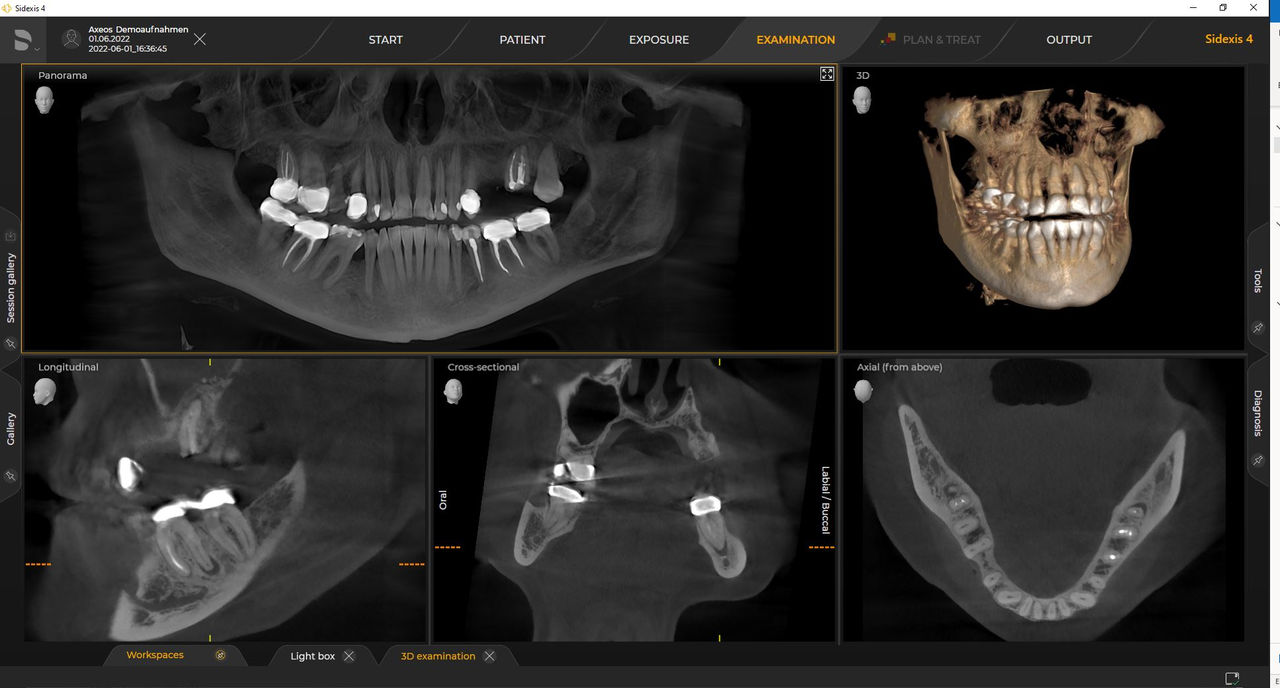

Los requisitos siguen aquellos del software de procesamiento de imágenes de Sidexis 4 y Axeos. Para obtener más detalles, consulte los requisitos del sistema Sidexis 4 y los requisitos de instalación de Axeos.

Las unidades 3D de Dentsply Sirona funcionan exclusivamente con Sidexis 4. Sin embargo, la migración de datos de Sidexis XG a Sidexis 4 es muy fácil. Sidexis 4 permite una experiencia digital completa con las últimas herramientas.